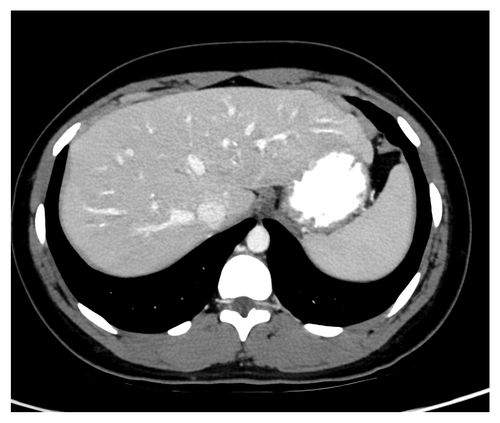

5.2 Qualitative evaluation with measured data

Fig. 7 and 8 show the results for two separate slices of Exam 1, a high-contrast clinical scan. Visually, results for the MSE-denoiser have smooth texture and lack detail. In contrast, BR- has more detail than MSE-denoiser, but with very nonuniform texture. The WGAN-VGG method recovers some texture and detail; however, the texture is not uniform.

From Fig. 7(7) and 8(8), TMGAN produces uniform texture, but with increased noise variance and with some details obscured by the texture. Alternatively, TMGAN-blended achieves the desired uniform texture, along with reduced noise and more visible detail. More specifically, the arrows in Fig. 7(7) indicate the detail recovered by TMGAN-blended even while maintaining the uniform target texture of TMGAN.